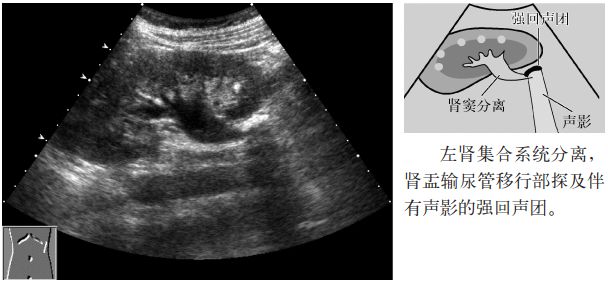

图10 输尿管结石(肾盂输尿管移行部)

1.扩张的输尿管内探及伴有声影的高回声。

2.伴有中心部回声(central echoes,central echo complex,CEC;肾窦)分离(肾积水)。